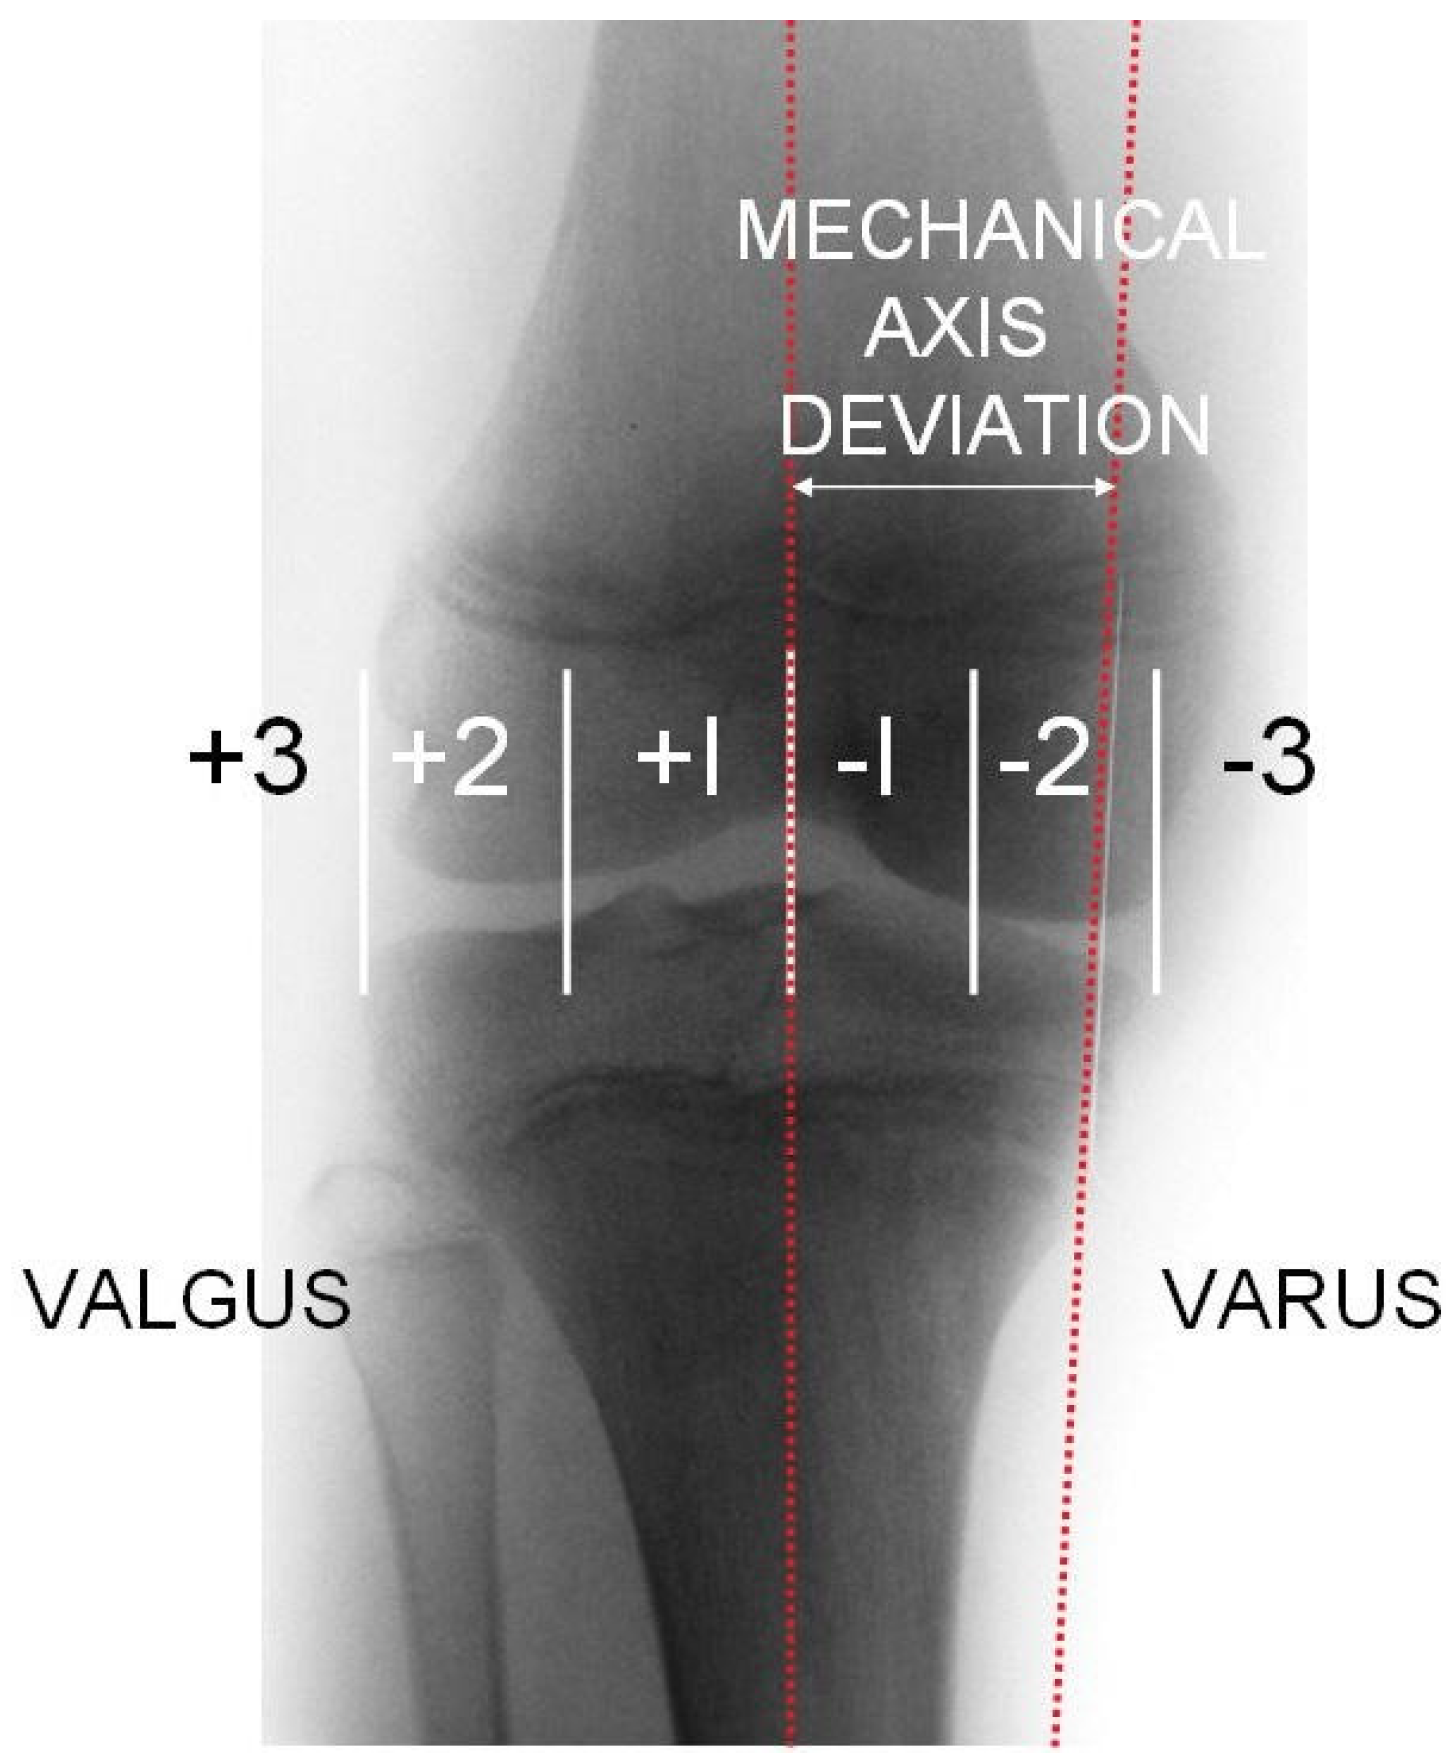

On the radiograph, the mechanical axis (Mikulicz line) was drawn from the center of the femoral head to the center of the talus, and the lateral and medial compartment of the knee joint was divided into three equal zones. If the mechanical axis intersected the middle third, a relative surgical indication was given; if it intersected the lateral or medial third, an absolute surgical indication was established (Figure 1). This technique and classification was described by Muller and Muller-Faber [14]. To determine whether the distal medial femur or the proximal medial tibia should be addressed, a deformity analysis was performed by measuring the mechanical lateral distal femoral angle (mLDFA) and the mechanical medial proximal tibial angle (mMPTA) (Figure 2). The location of the deformity was identified based on these measurements (Table 1). Radiographic measurements were performed independently by the attending orthopedic surgeon and a board-certified radiologist. The indication for surgery was based on the measurements obtained by the surgeon. For the purpose of this study, the reported values represent the mean of the measurements obtained by the surgeon and the radiologist.

Figure 1. Classification by Muller and Muller-Faber [14].